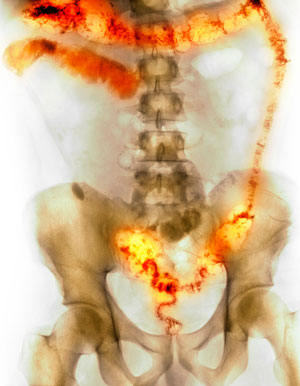

Figure 1: Colored x-ray image showing the inflamed and ulcerated colon of a man with inflammatory bowel disease. Severe cases such as this sometimes necessitate surgical removal of the colon. © SCIENCE PHOTO LIBRARY

Inflammatory bowel disease is a chronic condition that involves inflammation of the intestinal walls and causes symptoms such as bloody diarrhea and abdominal pain. GWASs have linked over 200 regions of DNA to the disease. Most of these regions do not actually code for proteins; instead they turn other genes, known as causative genes, on and off. These causative genes are the real culprits behind inflammatory bowel disease.